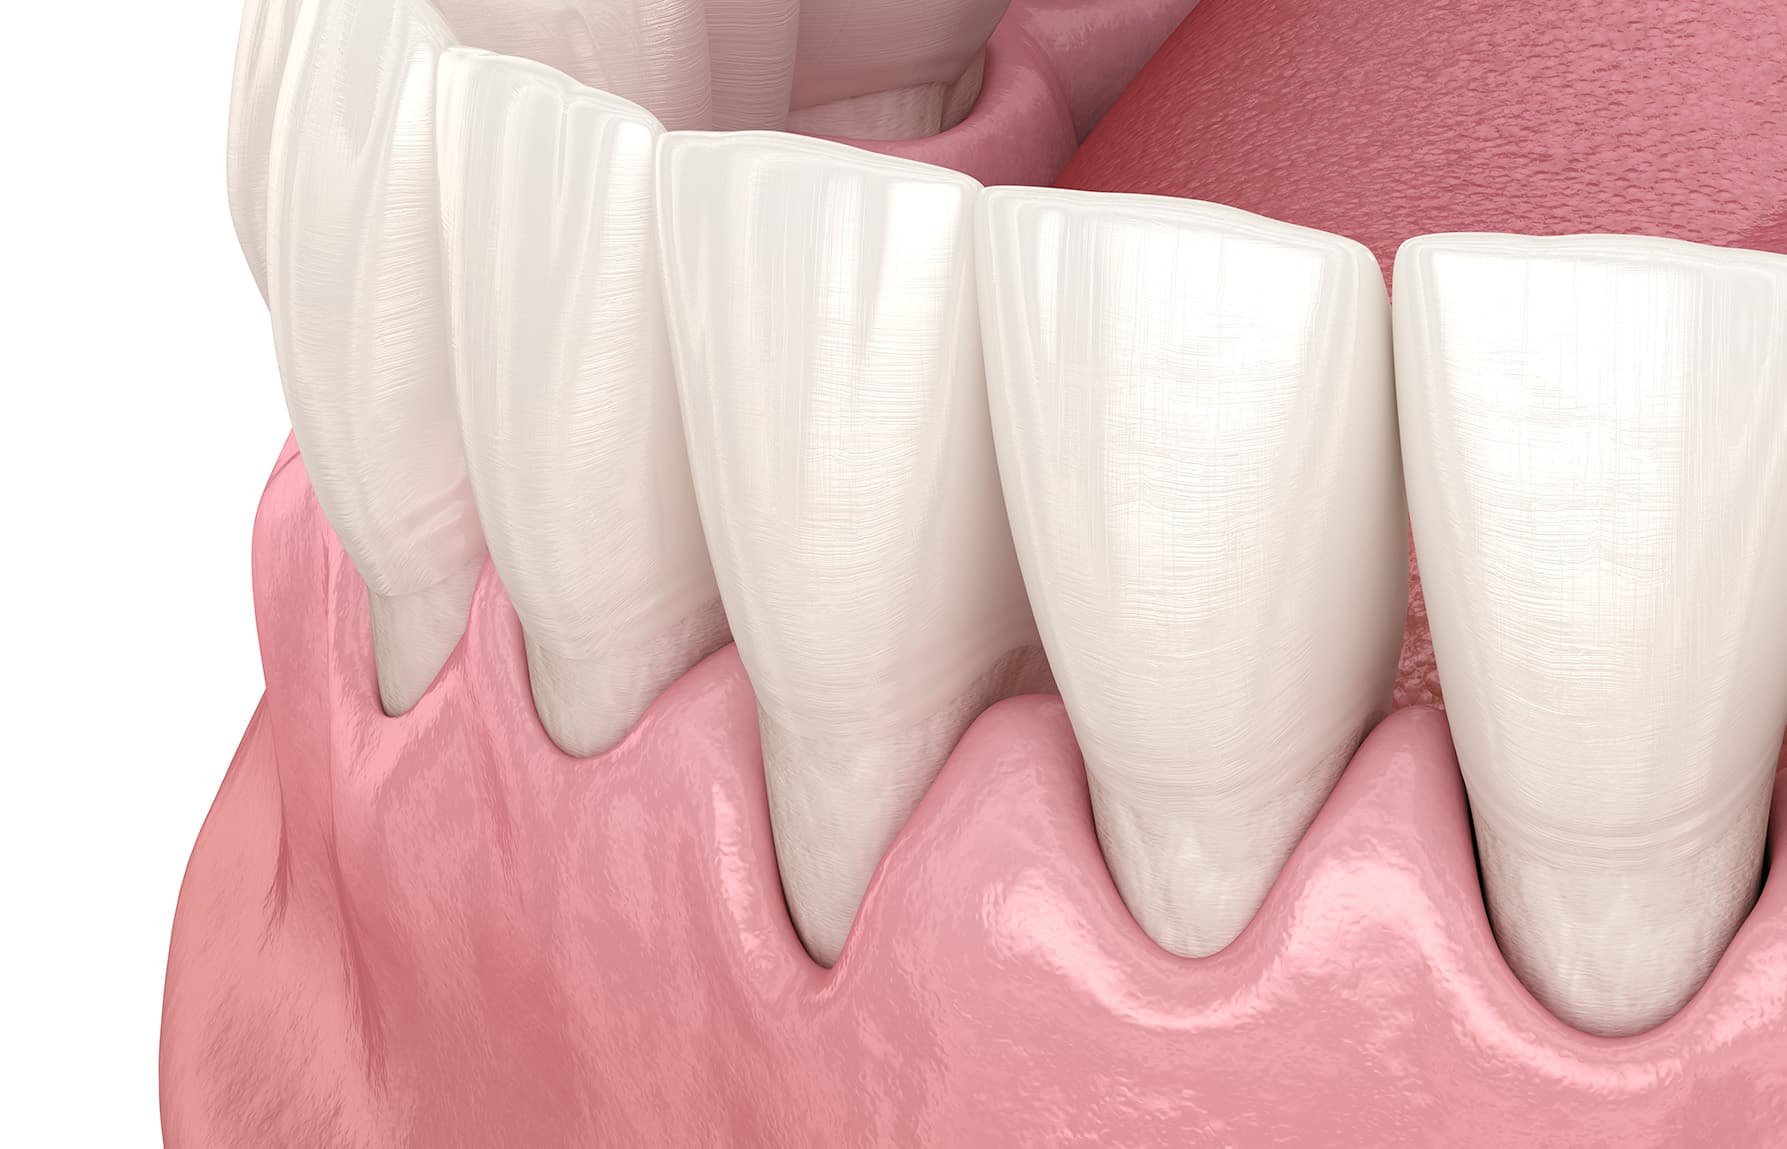

In een gezonde mond ligt het tandvlees netjes om de tanden en kiezen. Wanneer het tandvlees zich terugtrekt ontstaan gevoelige tandhalzen doordat de hals en de wortel van de tand of kies bloot komen te liggen. Op die plekken zit geen beschermend glazuur meer, waardoor het gebit erg gevoelig wordt voor invloeden als warm, koud, zoet en zuur. Het gedeelte wat bloot ligt veroorzaakt niet alleen tandpijn, maar is ook erg bevattelijk voor gaatjes (cariës).

Ontstoken tandvlees kan leiden tot teruggetrokken tandvlees. Gezond tandvlees is roze, ligt strak om de tanden en kiezen en bloedt niet als u eet of uw tanden poetst. Rood, gezwollen of bloedend tandvlees duidt meestal op ontstoken tandvlees. Tandplak op de overgang van uw tandvlees naar uw tand of kies en de plak die tussen uw tanden en kiezen zit, veroorzaken ontstoken tandvlees. Dit stadium wordt gingivitis genoemd.

Als u plak niet goed verwijdert, zorgen de bacteriën in de plak ervoor dat uw tandvlees verder ontstoken raakt. Niet verwijderde plak verkalkt tot tandsteen. Aan tandsteen hecht zich makkelijk weer nieuwe plak.Tussen de tand en het tandvlees zit een kleine ruimte (pocket). Omdat ontstoken tandvlees los komt te staan van de tanden en kiezen wordt die ruimte dieper. De ontsteking in de tandvleesrand kan zich uitbreiden in de richting van het kaakbot. Daardoor laat het tandvlees nóg verder los. Door de ontsteking gaan de vezels stuk en wordt het kaakbot afgebroken. Gevolg? Nog diepere pockets. Hierin verkalkt de tandplak gedeeltelijk tot tandsteen. Deze voortschrijdende ontsteking met afbraak van vezels en kaakbot heet parodontitis.

Door het ontstoken tandvlees zijn de tanden en kiezen los komen te staan en is het tandvlees teruggetrokken. De wortel ligt gedeeltelijk bloot. Parodontitis kan behandeld worden, waardoor het tandvlees weer gezond wordt. Eenmaal teruggetrokken tandvlees komt niet meer terug.